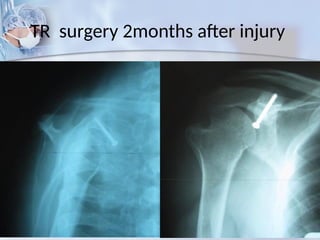

TR surgery 2months after injury

Good function, 14 mo po